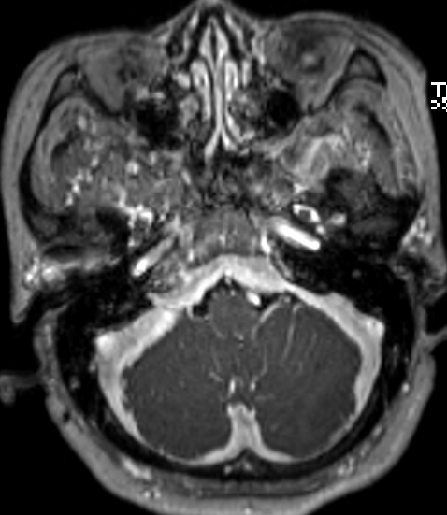

2013-8-2 MRI

2013-8-2 CT

腰穿脑压240